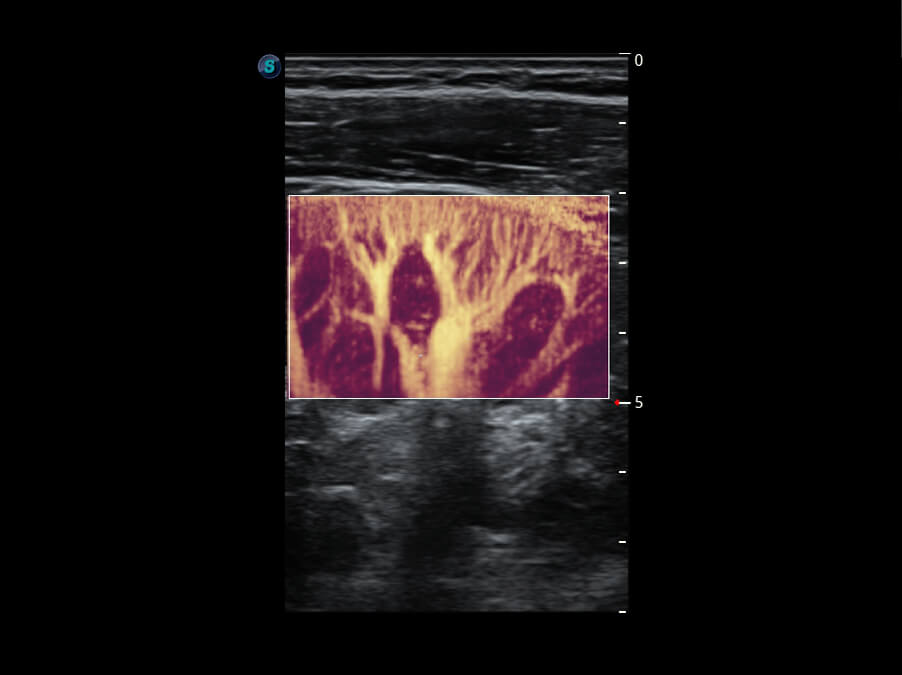

前端信号 真知灼见

S60探头工艺,从前端信号处理每一个环节采集无损声学数据,真实还原组织原貌,再现解剖细节。

• 腹部单晶体探头( C1-6A )

• 新型复合材料探头( 12L-A )

• 高分辨率容积探头( VC2-9A )